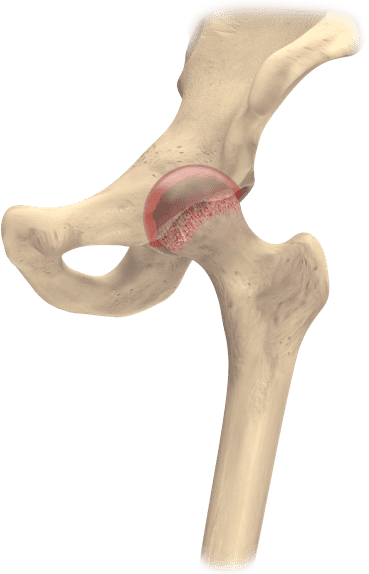

A hip may become diseased with arthritis or injured during a fall, which may reduce mobility and may cause pain during movement or even at rest. When arthritis wears away the cartilage, the hip bones may start rubbing together, which can be painful and may cause damage to the surface of the bones.The damaged bone and cartilage may cause joint pain and limit range of motion.

When the hip becomes diseased or injured, its natural balance and function may be disrupted, which potentially causes pain, limits mobility, or creates other medical challenges.